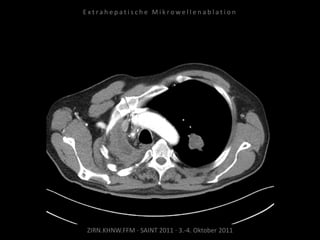

Ausgangsbildgebung:

CT vom 16.08.2010

Verlaufskontrolle:

CT 13.12.2010

Bildgebung vor MWA:

CT 14.03.2011

Situation:

Nur 1 Metastase, diese ist jedoch

progredient. Kritische Lage in

Herznähe.